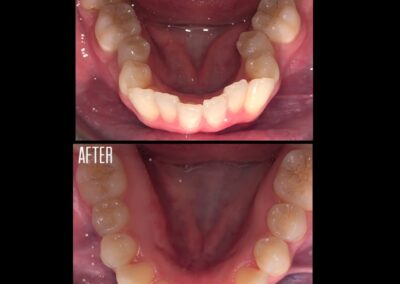

Gallery